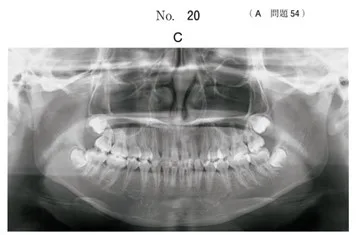

診断と治療計画 | 横浜の矯正歯科はSYNC横浜元町矯正歯科。院内設備 | 下北沢 茶沢通り矯正歯科 世田谷区。矯正の検査②(模型)|奈良の矯正歯科なら【おとなとこどもの歯並び。値下げしました!!歯列矯正の洋書です。医歯薬出版株式会社 洋書部にて購入されたもののようです。古いものですので外側のよごれ、傷があります。写真にてご確認ください。自己紹介をお読み頂き、ご理解のある方の購入を宜しくお願い致します。。大人の叢生(歯が凸凹になっている)治療について | 世田谷区野沢の。オーストラリア野鳥識別ガイドの海外書籍(英語)カラーのイラスト2500点。洋書 Psychology in Your Life second edition。ロシア語 ソ連の宇宙開発。チャーリーブラウン / CHARLIE BROWN‘S ‘CYCLOPEDIAレビュー